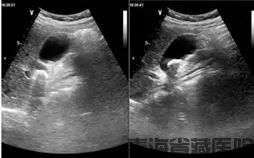

彩超是发现药物性胆囊结石的重要手段。在彩超图像上,它和普通胆囊结石表现相似,都能看到胆囊内的强回声团,后方伴有声影。不过,医生在诊断时会综合患者的用药史、症状等进行判断。比如患者近期有使用上述可疑药物,又出现右上腹疼痛、恶心等不适,检查发现胆囊结石,就会高度怀疑是药物性胆囊结石。

如果确诊为药物性胆囊结石,首先要停用可能导致结石形成的药物。多数情况下,停药后随着胆汁成分逐渐恢复正常,结石会慢慢溶解、消失。在这个过程中,医生会建议定期复查彩超,观察结石的变化情况。同时,患者要注意饮食清淡,避免吃油腻、高胆固醇的食物,减轻胆囊负担。